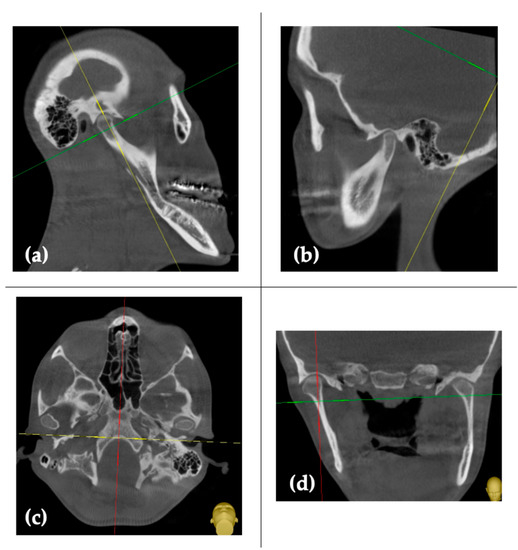

2. Case Report